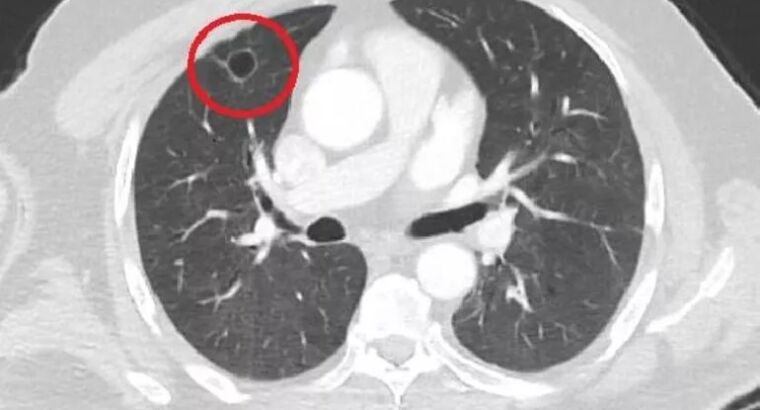

В результате тестов, проведенных одному пациенту, которому был поставлен диагноз рак легких и который был направлен на срочную операцию, было установлено, что это коронавирус имитировал рак легких.

Таким образом, было установлено, что коронавирус имитировал рак легких, и это впервые в мировой медицинской литературе. И стоит отметить, что после проведенного лечения против Ковид-19, у пациента лёгкие оказались чистыми.